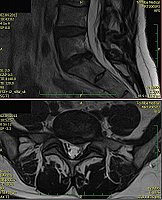

1. Žena, 48 let. Na MR patrná 8mm velká paramediální hernie L5/S1 vlevo s extruzí materiálu ploténky do epidurálního prostoru a útlakem kořenů L5 a S1 vlevo. Pacientce byla doporučena operace, kterou odmítla a zvolila alternativní postup s aplikací ozonu. Viz obr. 6a

Na kontrolním MR po 1 měsíci (po 2 aplikacích ozonu) periradikulárně je viditelné vymizení fragmentů v epidurálním prostoru a částečná retrakce meziobratlové ploténky. Subjektivně výrazná úleva, po 4 týdnech návrat do práce. Viz obr. 6b